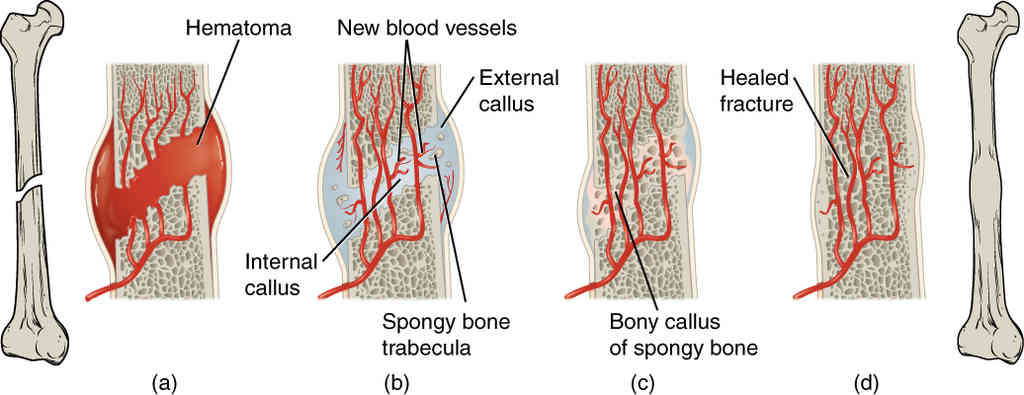

This page is under construction. For now, it is just a resource of the images found in the OpenStax Anatomy and Physiology Handbook. It wil slowly change into a revision tool. Each slide has a number. Use this to refer to the slide. When completed, it will have an unlabelled section, with labelled slides in parallel. On the unlabelled slides, write your answer and use the labelled slide to assess yourself. Keep track by also noting the number on each slide. Improvement at each attempt is important, more so than full marks on a first attempt.